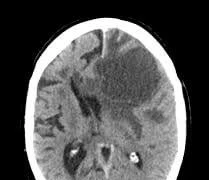

Bệnh nhân ung thư phổi giai đoạn IV có đột biến ALK, có 2 ổ di căn não đã hết hoàn toàn u sau 1,5 tháng điều trị thuốc ức chế ALK thế hệ 3: Lorlatinib.

Di căn não là một biến chứng thường gặp trong nhiều loại ung thư, nhưng đặc biệt phổ biến ở những bệnh nhân bị ung thư phổi. Khoảng 15 - 20% bệnh nhân ung thư phổi phát triển di căn não. Tỷ lệ di căn não não cao hơn ở ở bệnh nhân có đột biến gene EGFR và tái sắp xếp ALK, trong đó 50 - 60% di căn não trong quá trình bệnh.